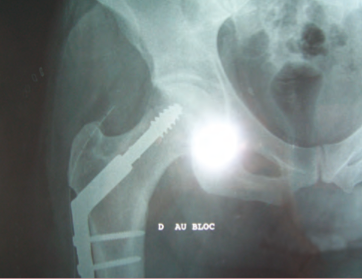

Radiographie : le clou.